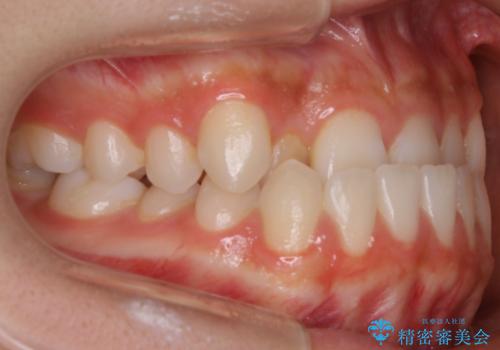

こちらの患者様の場合、上の前歯のガタつきが原因で口を閉じる際に上下の前歯の先端同士が先に当たってしまい、そこからさらに深く噛み込もうとすると下顎が前にずれていってしまうという、機能性の反対咬合であることが検査の結果わかりました。

そのため、まずは上顎の前歯のガタつきを改善していき、前歯が先に当たってしまうという症状を改善し噛み込む位置を後方の本来の位置に誘導する方法をとりました。

本来、正常な噛み合わせの場合は上顎の前歯が下顎の前歯より前に覆いかぶさるように噛み込んでくる状態が理想的です。

それに対して「反対咬合(受け口)」の場合は、下顎の前歯が上顎の前歯より前に出てきてしまう状態を指します。

その原因は ①骨格的問題 ②機能的問題 の2つに大きく分かれます。

原因が②であった場合は、手術を必要とせず口腔内ではの位置を変えてあげるだけで噛み合わせや顔貌を変化させることができる場合があります。